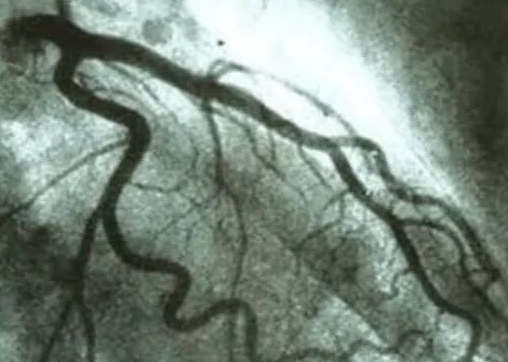

而第三大法宝,冠状动脉造影检查,则是通过造影了解房子内各个房间水管是否通畅?或者哪个房间的水管是否堵塞了,还是漏水了?也就是看心脏的冠状动脉血管是否狭窄或者是闭塞了,是否存在有心肌梗死了?